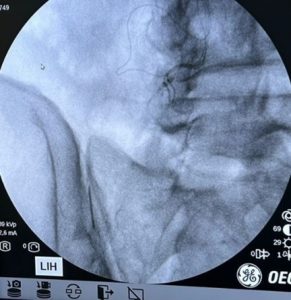

- Infiltraciones y radiofrecuencias: Son muy útiles para el tratamiento del dolor y mejorar la función de la articulación. Es un procedimiento muy poco invasivo, que se tolera muy bien y mejora mucho la sintomatología. Es un método de alivio rápido y eficaz del dolor y del bloqueo.